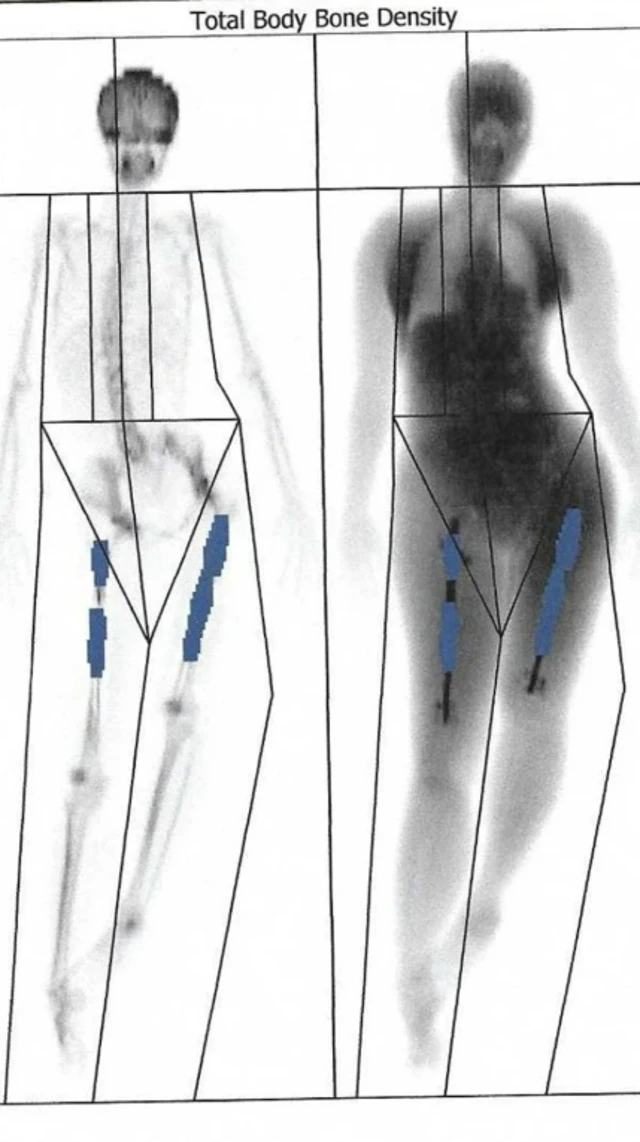

Elaine Fu waxaa lugaheeda ku yaalla calaamado midabkoodu xigo buluug mugdi ah, kuwaas oo ah xusuustii qalliin ay isku dheereyn leheed balse six un ku dhamaaday.

Markii la joogay laba bilood, lugteeda midig waxaa ku darsoontay 7 cm. Laakiin wax badan ayaa iska badlaay sidii caadig ahayd. Labada lugood ayaa kala gaabtay, taas ayaana sababtay in laf dhabartu ay qalloocanto gabadha.

Muddo lix todobaad ah kadib ayaa waxaa la baaray lafaheeda, waxaana la ogaaday in lugta midig lafaha ku jiray aysna koraynin.